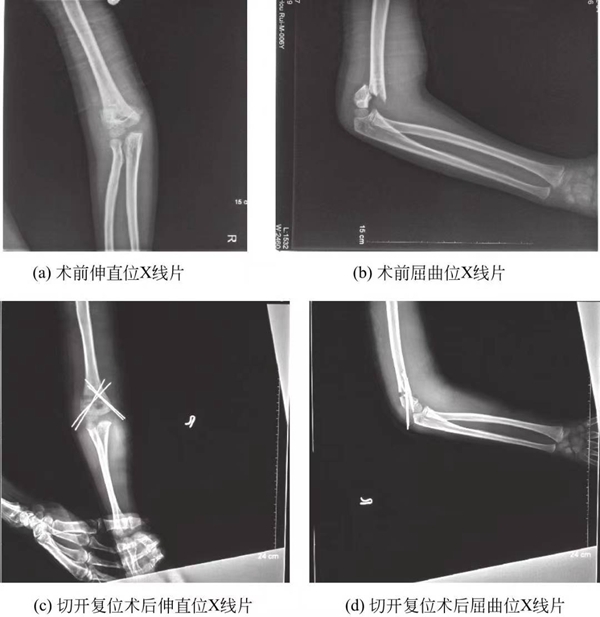

(3)Ⅲ型肱骨髁上骨折:所有的Ⅲ型肱骨髁上骨折复位经皮克氏针内固定是目前Ⅲ型髁上骨折的标准治疗方法。通常可闭合复位经皮克氏针内固定,但若软组织嵌入不能解剖复位或存在肱动脉损伤者需切开复位(图2)。

图5-3 肱骨髁上骨折术前术后X线片